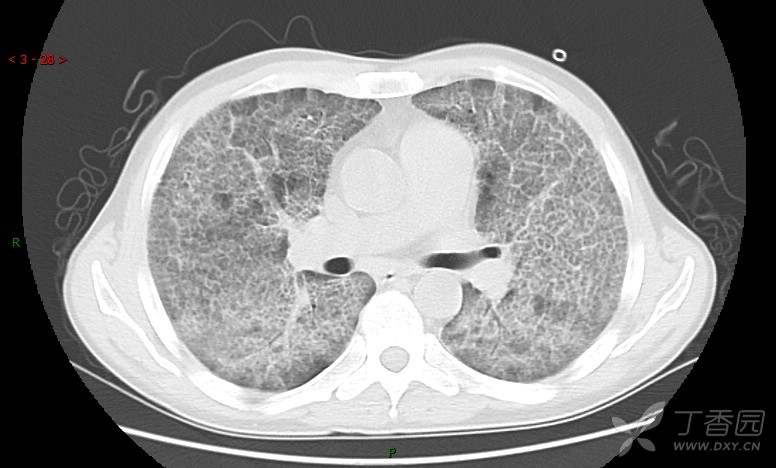

地图+铺路石征=PAP?那升高的CEA怎么说(病例3连发,附其他2例链接)

患者男,42岁,咳嗽半年余,加重伴憋喘2月余。

患者半年余前无明显诱因出现间断咳嗽,干咳为主,偶咳少量黄白痰,剧烈咳嗽或运动后可出现轻度憋喘,无高热、脓臭痰,无胸痛、咯血及晕厥,无低热乏力及盗汗,无心前区压榨感及夜间阵发性呼吸困难,初未在意,未予正规诊治。2月余前患者自觉上述症状较前加重,咳嗽、憋喘明显,黄白色粘痰略有增多,伴有发热,热前伴有畏寒、寒战,体温最高达38.9℃,先后就诊多家医院,入住重症监护室,未行气管插管,考虑“重症肺炎”,给予“美罗培南、复方磺胺甲噁唑”等药物抗感染,“卡泊芬净”抗真菌,并给予“甲泼尼龙”等药物治疗35天,经治疗后症状好转于2018-04-02出院。患者自出院后仅应用中药治疗(具体不详),并给予家庭氧疗,平素仍有间断咳嗽,咳少量黄白色粘痰,活动后憋喘明显,活动耐量差,以卧床为主。

肺内弥漫性网状结节影,PET-CT却无阳性病灶,这是?(附其他2例链接)